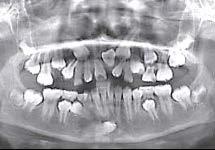

Acciones clínicas para el diagnóstico

En la práctica clínica, al hacer la revisión, uno de los signos clínicos motivo de alerta, correspondería a la falta de movilidad de los caninos deciduos cuando ya es tiempo en el intercambio dental,(caninos superiores 10 años ±9 meses, caninos inferiores 9 años ±9 meses)9 así como señalar si existe la ausencia de los mismos, la falta de espacio en el arco dental para la erupción de los caninos

permanentes, por el que el apoyo radiográfico inicial confirmará la posibilidad de una inclusión canina en proceso (Figura 16).

Diagnóstico radiológico

A partir de los 8 años, se puede observar radiográficamente el inicio de la reabsorción del canino deciduo (Figura 17).

El seguimiento del trayecto canino con un estudio radiográfico postero anterior, lateral de cráneo y ortopantomográfico, a partir de la edad señalada anteriormente, también es una herramienta efectiva que permite obtener un diagnóstico inicial, donde podrá observarse si se ha iniciado la reabsorción radicular del canino deciduo e identificar qué

dirección o trayecto está tomando el canino permanente (Figura 18).